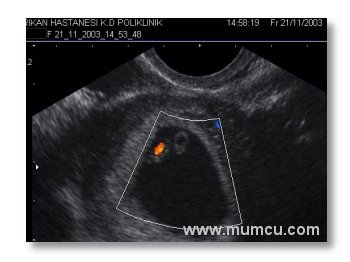

5 hafta 6 günlük gebelikte kalp atımlarının renkli doppler ile izlenmesi

Vajinal ultrasonografi